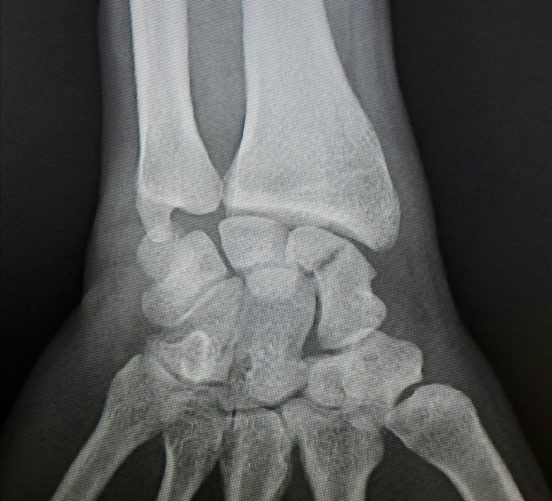

Radiografía de fractura de escafoides